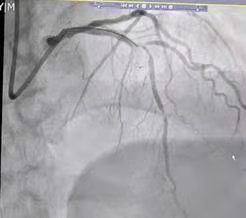

来自渭南市临渭区的患者杨某是首位获益者。患者杨某,80岁,以“胸部憋闷不适一周余”来渭南市第一医院心脏中心就诊,经心电图及抽血等检查后,显示为“急性下壁心肌梗死”,行造影检查结果显示:前降至与对角支分叉处及中段血管狭窄严重,右冠近中段严重狭窄。

图为患者三支血管病变,保守治疗风险较高,要分次手术,与家属充分沟通后行支架植入手术

在唐都医院张东伟教授团队充分的术前准备、精准操作下,在科室负责人梁兴盛医师、谢军芳副主任医师、王伟副主任医师介入团队的共同协作下,使用“crush”双支架技术,成功为患者实施了前降支与对角支分叉处支架植入手术,术后造影结果显示,患者堵塞的血管血流通畅,患者胸痛症状缓解。